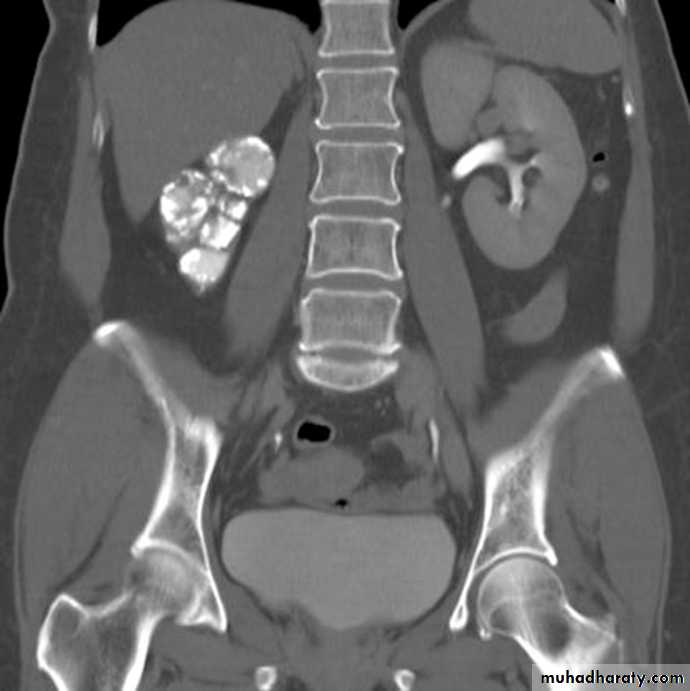

Horseshoe kidney:

• The kidneys fail to separate and they are almost invariably joined at their lower poles.

• Causes increase incidence of PUJ obstruction and stones formation.